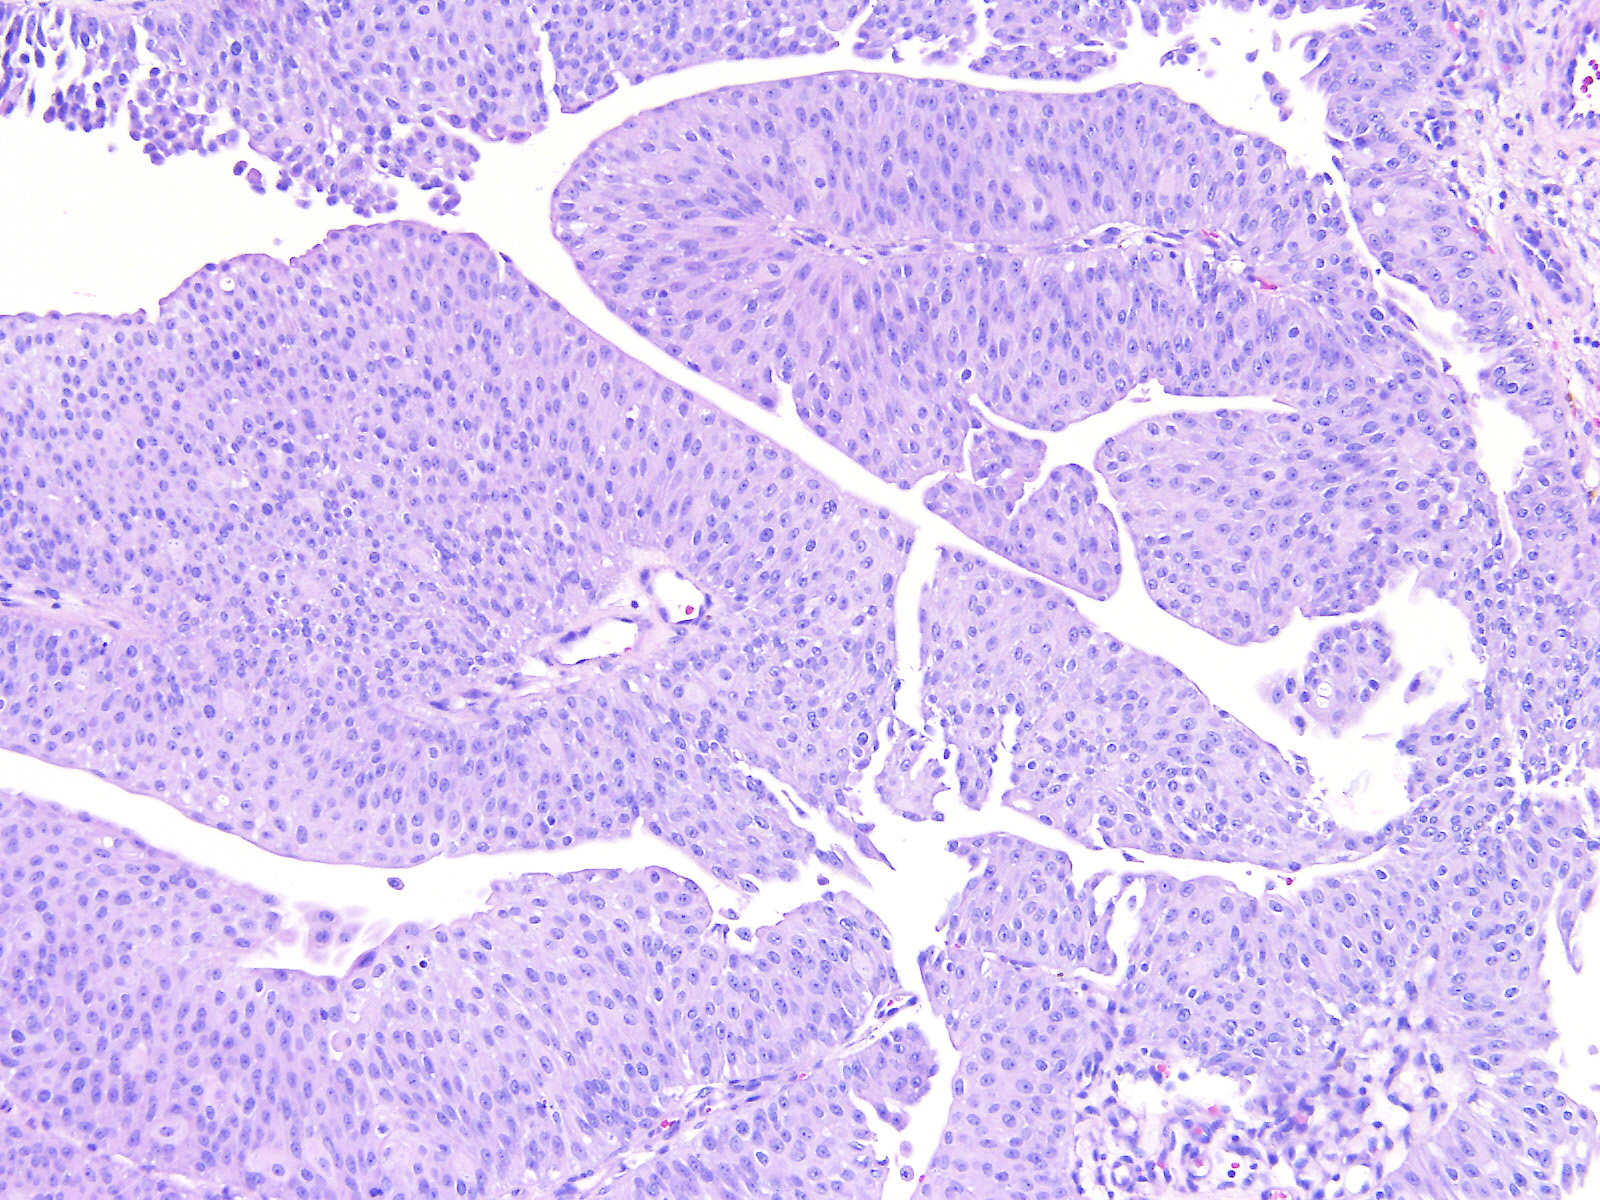

Bladder Papillary Lesions

Case ID: 559